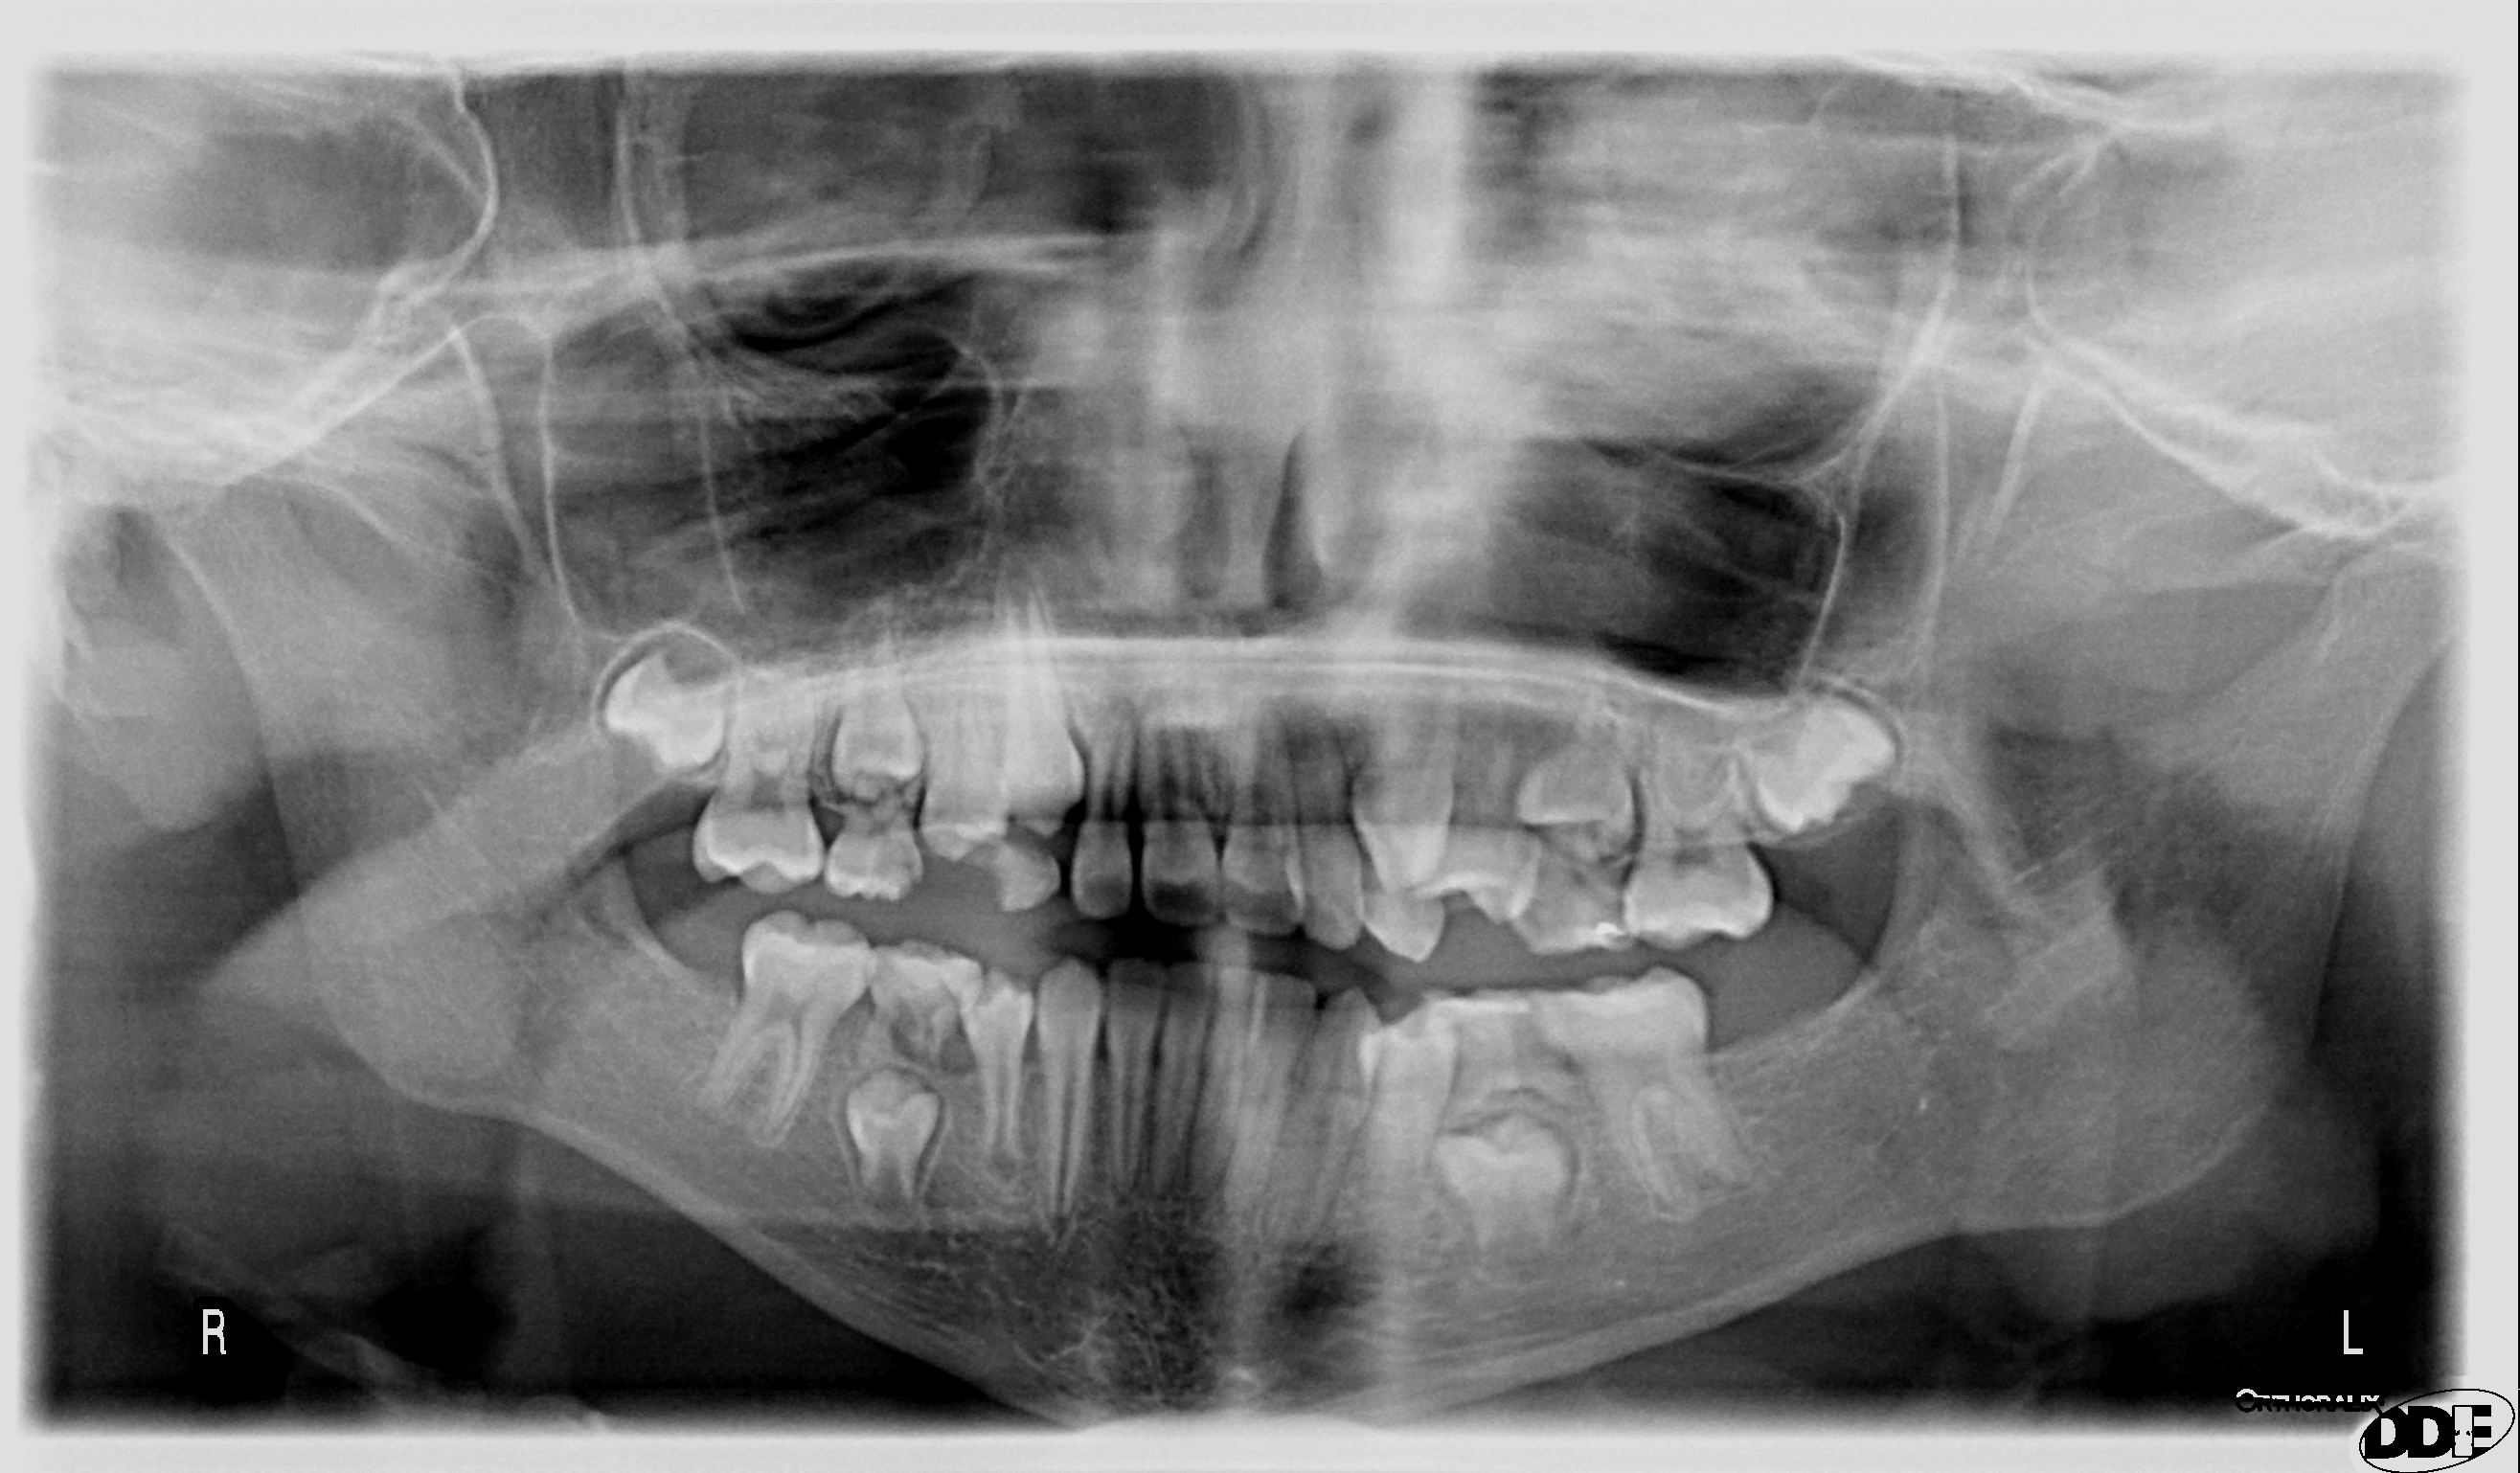

A mia figlia di 9 anni mancano i 2 settimi inferiori

Buongiorno, sono il papà di una bambina di 9 anni, da una panoramica ai denti ci siamo accorti che mancano i 2 settimi inferiori; cosa può portare questa anomalia negli anni a venire alla bocca della bambina?? grazie, Claudio